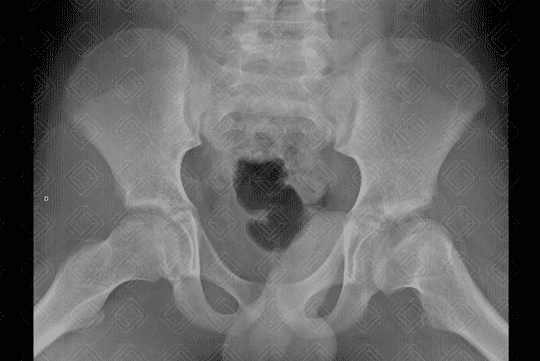

Texto alternativo para a imagem Figura 2. Créditos: Dra Elazir Mota - Rio de Janeiro/RJ

Descrição da lesão: Legg-Calvé-Perthes (necrose avascular idiopática).

Descrição das imagens: Radiografia de bacia em AP (figura 1) e Lowenstein ou posição de rã (figura 2): redução da altura e osteopenia da epífise femoral esquerda associada a colo femoral alargado e encurtado a este lado. Quadril direito sem alterações.

Doença de Legg-Calvé-Perthes: Necrose avascular (osteonecrose) idiopática da cabeça femoral. Seu pico de incidência é entre 2-14 anos de vida, mais comumente ao redor dos 6 anos. Os meninos são mais acometidos (5:1). A etiologia da doença permanece incerta.

• Radiografia do quadril: S empre realizar estudo em AP e Lowenstein (posição da rã). Numa fase muita aguda, os achados da osteonecrose na radiografia são sutis. Com o passar das semanas e meses, observamos redução da altura das imagens e lesões líticas e, mais tardiamente, fragmentação e destruição óssea;